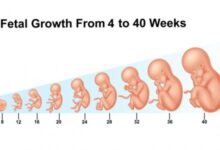

تعتبر فترة الحمل في الشهر الخامس من أكثر الفترات التي ترتاح فيها السيدة الحامل، وذلك بسبب التخلص من أغلب أعراض الحمل المزعجة، ويبدأ توقيت هذا الشهر من الأسبوع الثامن عشر إلى الأسبوع الواحد والعشرين، ويزداد نمو الجنين خلال هذا الشهر بشكلٍ ملحوظ، كما يزداد حجم بطن الأم بالتزامن مع زيادة وزن الجنين وحجمه، وسيتم في هذه المقال عرض التطور في شكل الجنين وحجمه في الشهر الخامس من الحمل.

- الأسبوع الثامن عشر: يصل طول الجنين خلال هذا الأسبوع إلى ما يقارب ال14 سم، ويصل وزنه إلى حوالي 141 غراماً، وتشعر الأم خلال هذه الفترة بحركة الجنين وركلاته داخل الرحم، كما يمكنها الخضوع لفحص الموجات الفوق صوتية وملاحظة جنينها يتثاءب، بالإضافة إلى ذلك، يتطور الجهاز المناعي لدى الجنين في هذا الأسبوع.

- الأسبوع التاسع عشر: يصل طول الجنين خلال هذه الأسبوع إلى حوالي 15 سم، ويصبح وزنه يقارب ال226 غراماً، ويكتمل نمو اليدين والرجلين، كما ترتبط الخلايا العصبية لتصل بين الدماغ والعضلات.

- الأسبوع العشرون: يصل طول الجنين في هذا الأسبوع ليصل حوالي 16.5 سم، ويزداد وزنه بشكل ملحوظ ليصبح يقارب ال 283 غراماً، وعلى الرغم من أن حجمه كبير، إلا أنه ما زال قادراً على التحرك بكل حرية في رحم الأم، ويستطيع الأهل هنا تحديد نوع الجنين من خلال التوجه إلى الطبيب المختص، والخضوع للموجات الفوق صوتية.

- الأسبوع الواحد والعشرون: يصل طول الجنين في هذا الأسبوع ليصبح حوالي 18 سم، ويصبح وزنه يقارب ال311 غرام، وبالرغم من التحرك بشكل مستمر، إلا أنه ما زال يحصل على ما يقارب ال12 إلى 14 ساعة من النوم يومياً.